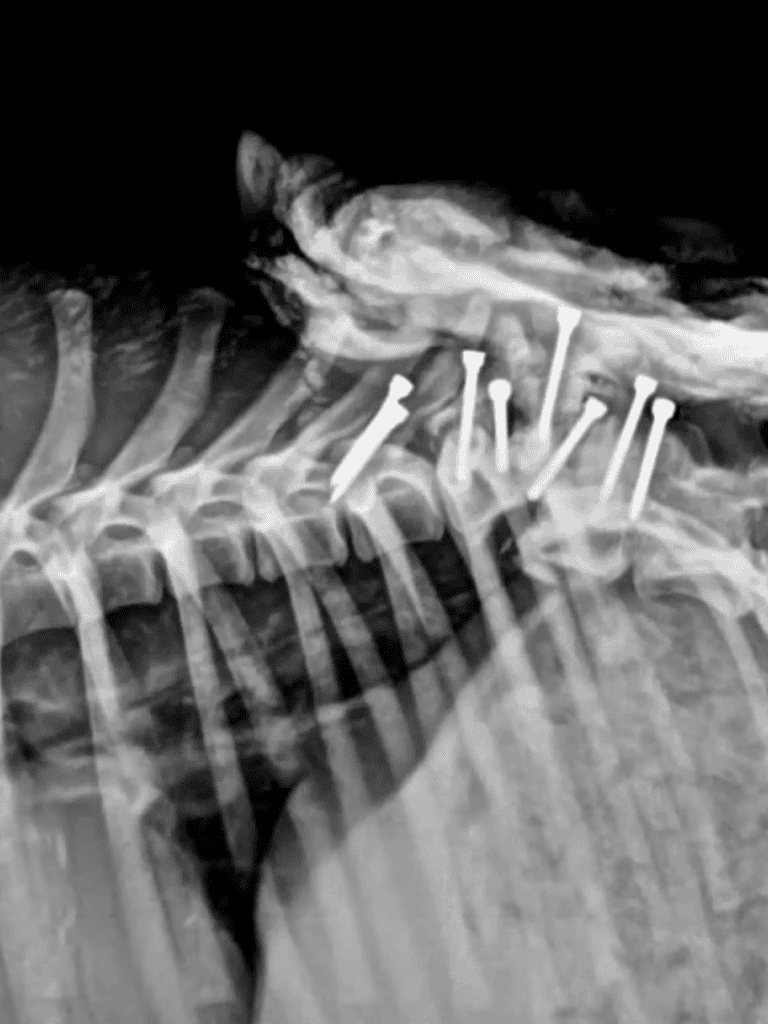

Eva’s spine was irreparably damaged. X-rays and ultrasound showed prior surgery, suggesting her owner abandoned her after a failed recovery.

Eva’s spine was severely injured, and infection was spreading. Urgent surgery was needed to remove bone fragments and cleanse her wounds. It wouldn’t restore her ability to walk but could save her life.